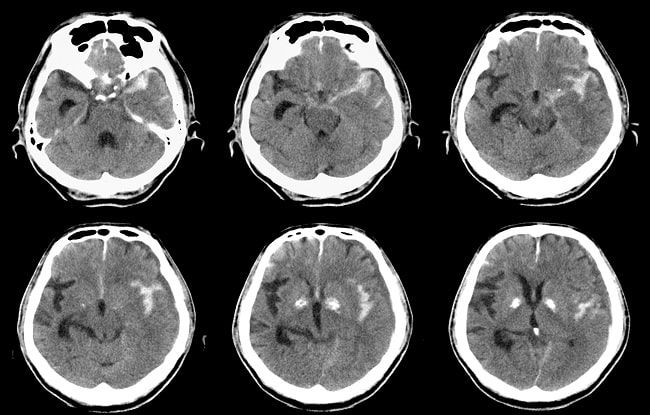

Penegakan diagnosis dan penatalaksanaan kasus SAH spontan yang cepat dan tepat sangat penting untuk dapat menurunkan angka mortalitas dan morbiditas. Diagnosis SAH spontan dapat ditegakkan secara pasti dari hasil CT scan kepala non kontras. SAH spontan perlu dicurigai pada pasien dengan keluhan sakit kepala hebat, penurunan kesadaran, kaku kuduk, dan/atau parese nervus kranialis.[1,2]